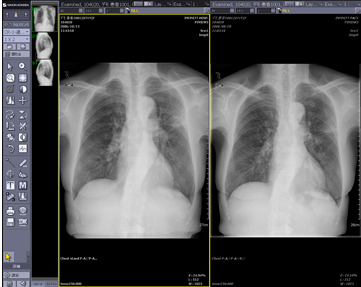

ハンギングプロトコルとは,ユーザーの読影目的に合わせ,画面構成をカスタマイズする機能のことです。モダリティや検査部位,ツールバー,サムネイルまで画面構成を設定することが可能です。過去画像比較(図4)や縦隔・肺野比較(図5),マルチモダリティ表示(図6)や3D画像作成機能(図7)までもがワンクリックで意図した画面レイアウトで表示され,迅速で簡単な読影環境を提供します。ハンギングプロトコルの設定は,ユーザーごとの設定であるため,ハンギングプロトコルをフル活用することにより,自分だけのオーダメイドPACSとして使用することができます。

![]() 図4 胸部過去比較表示 |